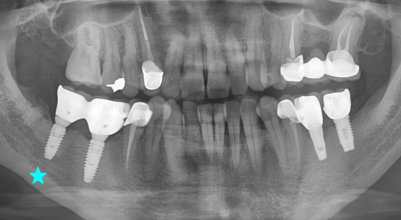

Internal Bone Level - Tapered

The IB-T implant system offers a flexible solution for all indications and esthetic outcomes. It is a submerged type implant that has an internal hex 11˚ taper connection. With tapered body design, it allows excellent primary stability, and it can be applied to any situation as it has various diameters, lengths and prosthetic line-up.